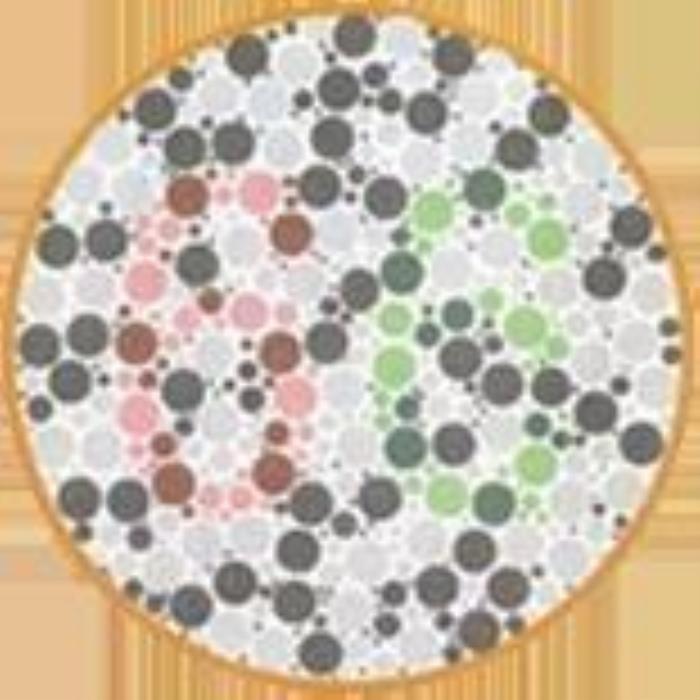

终极测试!!下面这张图你看到了什么数字?

结果:

左图:全色弱者及正常者读不出来,红绿色盲者及红绿色弱者大多能看到5

右图:正常者及全色弱者大多找不到,红绿色盲者及红绿色弱者容易找到